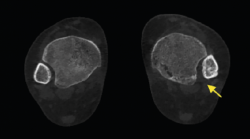

mact.1301.fs2105003-figura9.png

Figura 9. Se aprecia un desplazamiento lateral de los sesamoideos en deformidad del hallux valgus.

• Valoración rotacional del primer radio y desplazamiento de los sesamoideos. Valoración de la deformidad y rotación del primer radio, así como el desplazamiento lateral de los sesamoideos (Figura 9).